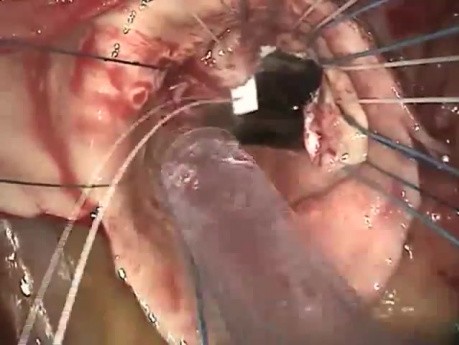

Rekonstrukcja opuszki i aorty wstępującej - cały...

Materiał przedstawia zabieg rekonstrukcji opuszki i aorty wstępującej. Zabieg ten zalecany jest wśród pacjentów kwalifikowanych do zabiegu operacyjnego z powodu tętniaka aorty wstępującej i z niedomykalnością...

Rekonstrukcja opuszki i aorty wstępującej

Film prezentuje zabieg rekonstrukcji opuszki i aorty wstępującej. Zabieg ten zaleca się pacjentom kwalifikowanym do zabiegu operacyjnego z powodu tętniaka aorty wstępującej i z niedomykalnością zastawki...